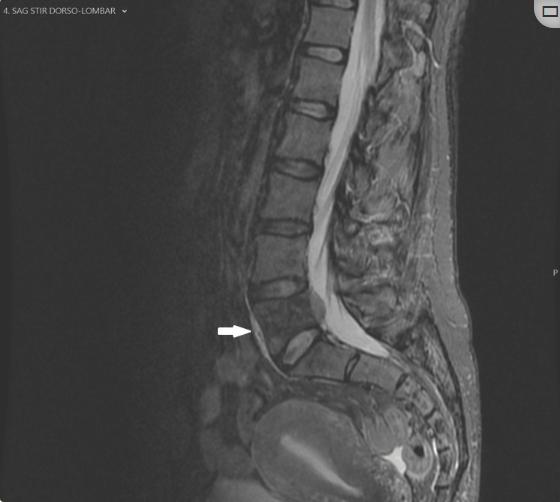

图5、核磁共振,搅拌序列

MRI上,病灶在STIR序列上无明显高信号